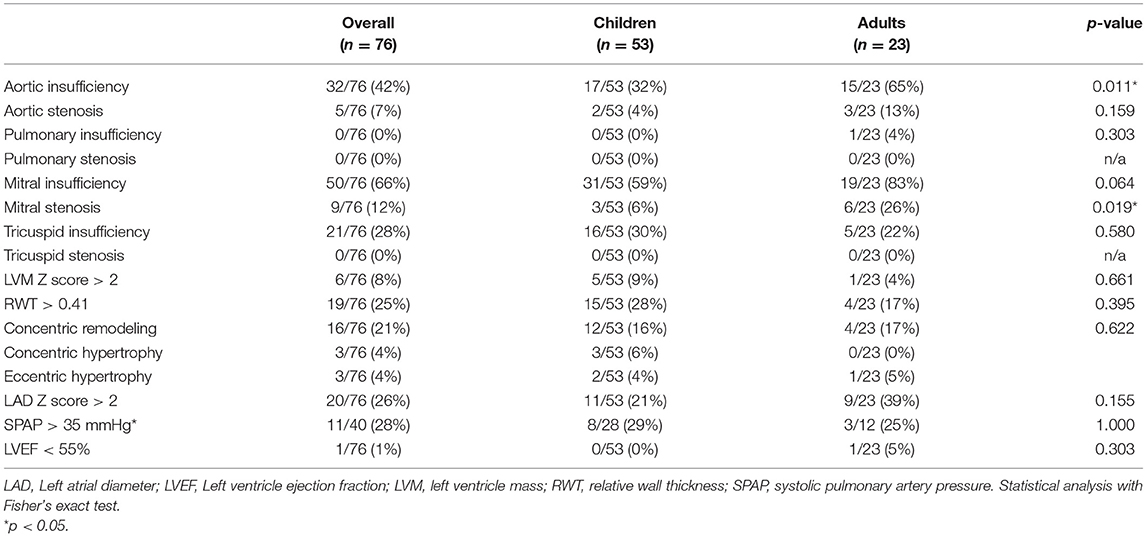

Valvular Disease

Among the 76 patients included in this study, left side valvular disease was a frequent finding, with mitral and aortic thickening being reported in most patients in all four MPS types (Figure 1). Furthermore, mitral and aortic insufficiency, mostly mild, were frequently found in patients with MPS I, II, and VI, but were also observed in a significant proportion of patients with MPS IVA. To a lesser extent, tricuspid valve thickening and insufficiency were also present in patients with MPS types I, II, and VI. Heart valve involvement was both more prevalent and more severe in adult patients (Figure 2; Table 3).

Figure 1. Prevalence of heart valve abnormalities in MPS types I, II, IVA, and VI, including both treated and untreated subjects.

Table 4. Prevalence of echocardiographic abnormalities at the last available echocardiogram, including both ERT treated and untreated subjects.

In this study, we assessed the prevalence of cardiac manifestations in a cohort of patients with MPS I, II, IVA, and VI; which included mostly patients treated with ERT. In agreement with previous reports (3, 17–20), valve involvement comprised mainly left-sided valves and affected a high proportion of patients. Mitral valve involvement was more common than the aortic valve in the four MPS types. Valve involvement, especially aortic insufficiency and mitral stenosis, was more commonly observed in older patients. We could not identify any significant worsening or improvement of valve pathology after ERT. It is widely accepted that ERT has limited impact on valve abnormalities of patients with MPS (13, 21–25), probably due to poor tissue penetration and irreversibility of the valvar damage. Nevertheless, it may have a role in preventing or delaying its appearance when treatment is started very early, as suggested by studies with sibling pairs and animal models (26, 27).